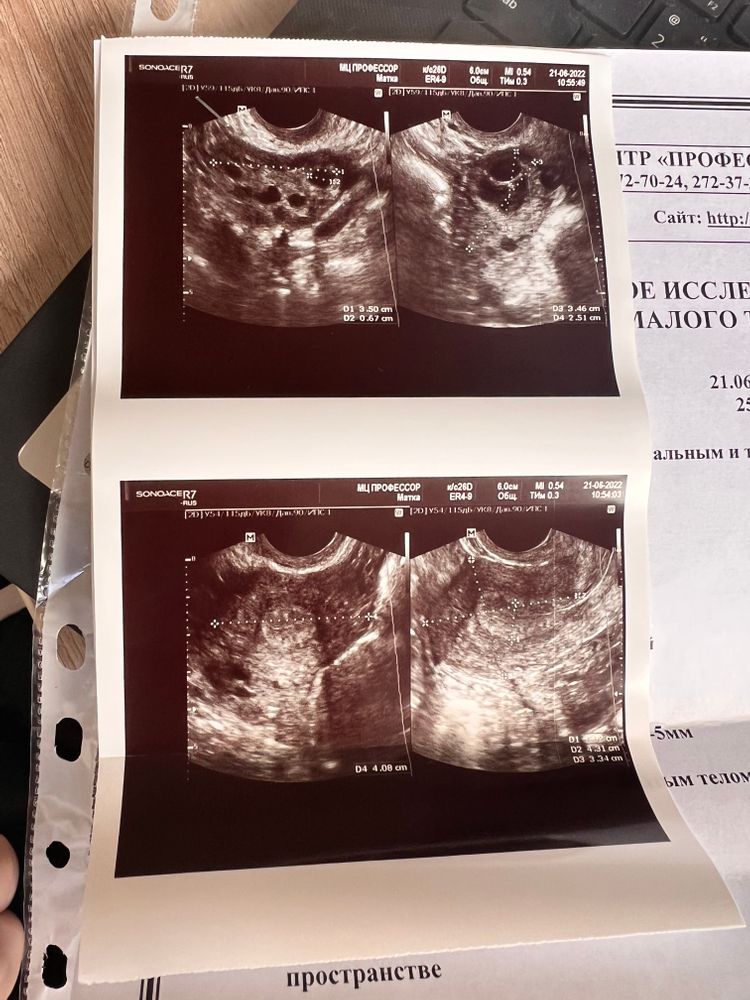

RM, эх, спасибо большое 🙏🏼🥲 остаётся только надеяться. Но я думаю, что наверное такой большой уже не лопнувший фолликул (((( наверное уже желтое тело. Кстати, на узи ещё показало, что нет свободной жидкости. Врач сказала вот что «Обьем свободной жидкости и время её обнаружения могут быть различными. Точнее об овуляции говорит жёлтое тело и строение эндометрия» а по поводу моего вопроса про ПА и не поздно ли- «Секс никто не отменял)яйцеклетка жизнеспособна 36-48 часов с момента овуляции» 😀 вот и думай теперь

УЗИ 8 недель Жёлтое тело 24 мм на 21 дц